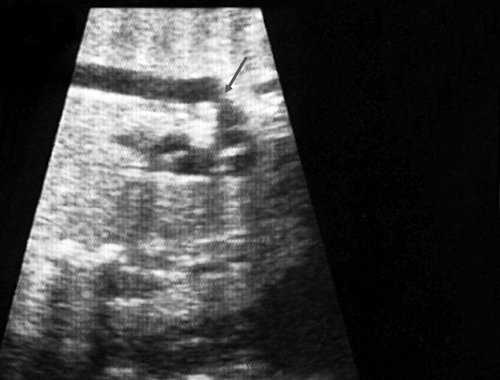

Первая причина не диагностированной коарктации аорты это морфогенез патологии и теория первичного нарушения развития дуги аорты. Теория была предложена в 1828 г. [11]. Автор считает, что данная патология связана с недостаточным соединением 4 и 6 дуги аорты с нисходящим ее отделом. Поэтому перешеек - это место, где наиболее часто локализуется участок сужения [12], так как оба отдела образуются из разных эмбриональных зачатков. В норме область перешейка аорты равна 2/3 диаметра восходящего отдела аорты (рис. 1).

Рис. 1. Восходящий отдел, дуга и нисходящий отдел аорты плода в режиме энергетического допплера в норме.

Согласно "теории дуктальной ткани" коарктация аорты возникает в результате миграции гладких мышечных клеток протока в предуктальную аорту, с последующей констрикцией и сужением просвета аорты [4]. При формировании коарктации аорты в области перешейка сохраняется сужение различной протяженности и формы (рис. 2, 3). Наиболее часто это проявляется в виде локальной перетяжки, выше или ниже которой диаметр аорты сохраняется в норме.

Рис. 2. Ультразвуковое исследование восходящего отдела, дуги и нисходящего отдела аорты. Стрелкой указано место сужения.